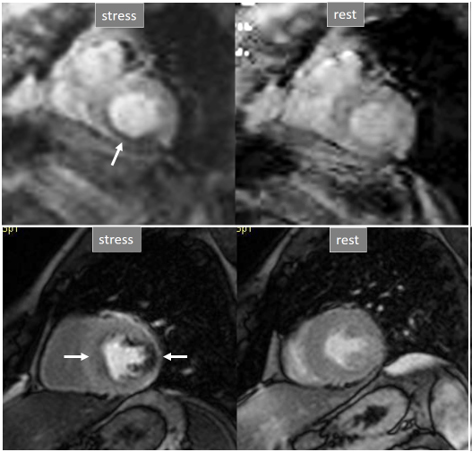

A not infrequent finding is a diffuse, annular, transient, subendocardial defect not present at rest (Fig. 9), which, in the absence of any recognizable obstructive lesion in an epicardial coronary artery, has been deemed to correspond to diffuse microvascular dysfunction (MVD) [41, 42]. CMR perfusion is sensitive to both the downstream effects of discrete epicardial stenoses and those due to disturbances of coronary microcirculation, and subendocardial hypoperfusion is on the pathophysiological basis of each one. For this reason, theoretically, a global, inducible subendocardial defect, could also be due to multivessel epicardial disease with balanced ischemia. In practice, however, this latter instance presents with extensive but heterogenous defects in terms of intensity, persistence and transmurality and, not rarely, also with perfusion defects at rest (Fig. 10A). Importantly, an accompanying induced contractile disfunction may be found in particularly impaired regions (Fig. 10B), a finding which is never seen in MVD.

Fig. 9.Microvascular defect. Circumferential subendocardial perfusion defect at stress, not present at rest, in the absence of LGE, in a patient without significant epicardial coronary lesions at angiography (right panels).

Fig. 10.Multi-vessel perfusion defect. (A) Global stress hypoperfusion in a patient with multivessel CAD. Observe the non-uniformity of the defect, with different degrees of intensity and transmurality and, also, with the presence of a defect at rest (arrow), in the absence of LGE. (B) End-systolic frames from cine studies at the same level of the perfusion slices showing inducible antero-septal hypokinesia during stress (arrows).